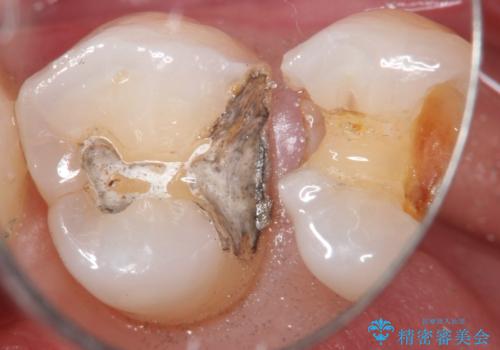

- 定期検診にて、奥歯の頬側歯肉にサイナストラクトが発見された患者様です。

根管治療から歯冠修復まで行っております。

サイナストラクト(瘻孔)から原因歯を特定し治療を行っております。根管治療を行った歯牙は破折リスクが高くなるため被せものによる治療を提案しております。